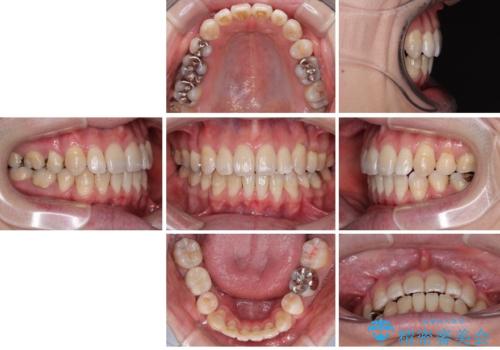

少しずつ前歯を後ろに下げていくことで、横顔のラインが整い、口元の“出っ張り感”が解消。

治療後には「自然に笑えるようになった」と嬉しいお声をいただきました。